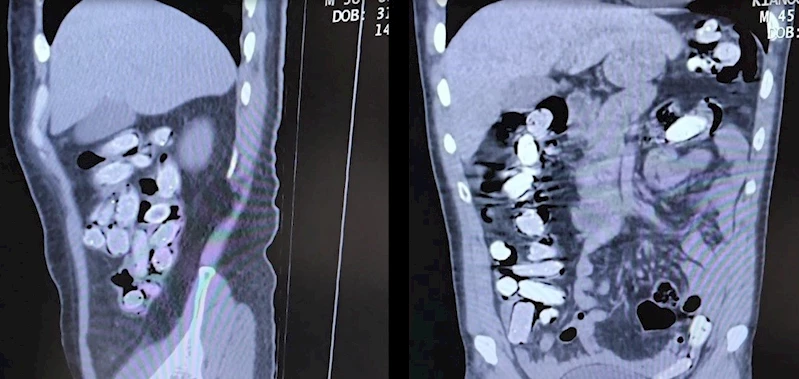

Bitlis’te yapılan operasyonda durumundan şüphelenen 2 yabancı uyruklu şahsın mide ve bağırsaklarında 1 kilo 340 gram uyuşturucu çıktı.

Bitlis Valiliğinden yapılan açıklamada, Emniyet Müdürlüğü Narkotik Suçlarla Mücadele Şube Müdürlüğü ve İstihbarat Şube Müdürlüğünce uyuşturucu ile mücadele kapsamında elde edilen istihbari bilgiler doğrultusunda, Bitlis merkezde durdurulan bir otobüste yolcu olarak seyahat eden yabancı uyruklu 2 şahsın yakalanarak gözaltına alındığı belirtildi. Tatvan Devlet Hastanesine sevk edilen şüphelilerin röntgen ve tomografi görüntülerinde mide ile bağırsaklarında çok sayıda yabancı cisim bulunduğu tespit edildi. Yapılan tıbbi müdahale ile şüphelilerin paketleyerek yuttuğu toplam 96 adet daralı ağırlığı 1 kilogram 340 gram Afyon sakızına el konuldu. Şüpheliler, çıkarıldığı adli mercilerce tutuklanarak cezaevine gönderildi.